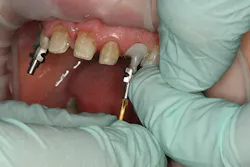

A 32-year-old white female presented for a cosmetic consultation. The patient reported that during her teenage years she had received orthodontic treatment to move her permanent maxillary canines mesially into the spaces that should have been occupied by her congenitally missing lateral incisors. She stated that her dentist, orthodontist, and oral surgeon had decided to place endosseous implants in the canine spaces due to the greater availability of bone in comparison to the bone available in the lateral positions (figure 1). As she grew older, she had become increasingly dissatisfied with the appearance of her smile and was seeking a more updated and esthetic solution (figure 2).

Figure 2

A comprehensive cosmetic, radiographic, and functional evaluation was performed.1 The patient was able to identify the major concerns leading to her dissatisfaction with her smile, including the presence of multiple diastemata, tooth proportion improprieties, unnatural emergence profile of her implant restorations, and her desire for a whiter smile (figure 3).2

Figure 3